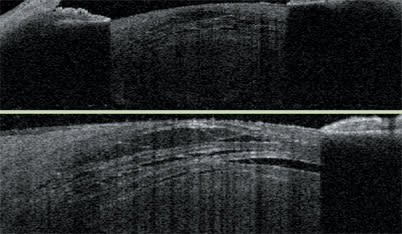

Here, I explain some of these uses, beginning with corneal transplantation using the femtosecond laser. The Visante OCT has allowed us to rapidly improve our techniques by enabling us to see corneal incision cross-sections and better assess our results. As a result, deficiencies associated with the "top-hat" approach to penetrating keratoplasty became clear. The "zigzag" approach seems to be an effective alternative as it resists leakage and doesn't require sutures to be as tight.

The Visante OCT provides a high-resolution image of the cornea and measurement of its dimensions after a "top-hat" approach to corneal transplant.

This is a high-resolution postoperative corneal scan of a "zigzag" transplant incision. The angling down, the lamellar cut and angling again are visible.

The Visante OCT also aids viewing of Descemet's-stripping endothelial keratoplasty (DSEK). The surgeon can see the interface and document the flap depth.

The Visante OCT is useful for determining if Descemet's-stripping endothelial keratoplasties are properly attached. This image also shows the inevitable meniscus-shaped cut and a relatively ragged trephine-induced edge.

Using the Visante OCT system to monitor Descemet's-stripping endothelial keratoplasties, surgeons have learned that the donor tissue typically continues to thin for approximately 3 months, affecting patients' vision. This image also shows the quantification of the donor tissue depth at various points.